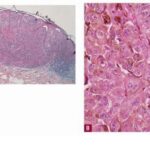

Histopathology of Nodular Melanoma and Common Vertical Growth Phase (Tumorigenic Melanoma) Architectural Features. In a typical tumorigenic melanoma, there is contiguous proliferation of neoplastic melanocytes in the dermis forming a tumor mass that is larger (usually much larger) than the largest nest in the |

Perhaps the best-known single criterion for melanoma is the upward pagetoid extension of tumor cells into the epidermis overlying the melanoma. However, this pagetoid melanocytosis or pagetoid spread is not specific for melanoma (152). Although in nodular melanoma, permeation of the epidermis with tumor cells may be absent or may be limited to that portion overlying the dermal tumor, lateral extension of melanoma cells in the epidermis and papillary dermis beyond the confines of the dermal tumor is seen in the adjacent nontumorigenic compartment of complex primary melanomas [SSM, LMM, acral-Ientiginous melanoma (ALM)]. This phenomenon greatly aids in histologic recognition of these tumors, and, conversely, the recognition of nodular melanomas, which lack this adjacent component, may be difficult. For this reason, nodular melanoma may be difficult or impossible to distinguish from a metastatic melanoma in the skin, and when such a tumor is amelanotic, the distinction from other cutaneous neoplasms may be impossible without immunohistochemistry. |

Cytological Features. The tumor cells in the dermis show great variation in size and shape. Nevertheless, two major types of cells can be recognized; an epithelioid and a spindle-shaped cell type. Many tumors show both types of cells, but usually one type predominates. Generally, the lentiginous forms of melanoma (e.g., LMM and ALM) tend to show a predominance of spindle-shaped cells in their invasive dermal components, whereas superficial spreading and nodular melanomas tend to be composed largely of epithelioid cells . The epithelioid type of cell tends to lie in alveolar or nested formations and the spindle-shaped type of cells in irregularly branching formations. The alveolar formations of the epithelioid cells are surrounded by thin fibers of collagen containing a few fibroblasts. Tumors in which spindle cells predominate may resemble sarcomas or other spindle cell tumors but in most cases differ from them by the presence of junctional melanocytic activity. |